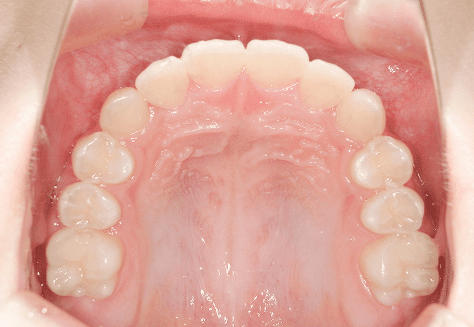

H.A

治療前

治療後

主訴

正中がずれているのが気になる。ちゃんと噛めていない。

診断

上下両側第二小臼歯先天欠如・上顎前突

年齢/性別

10代/女性

抜歯部位

必要に応じて乳歯抜歯

使用装置

6か月間エッジワイズにて下顎第一大臼歯の近心傾斜改善→上下インビザラインへ移行

保定装置

上下ビベラリテーナー

料金

初回資料採得・・・・・・・15,000円

診断料・・・・・・・・・・33,000円

動的治療終了時資料採得・・5,500円 -

基本料金

936,000円

診察料金

ワイヤー時:5,500円×4回

インビザライン時:1,100円×21回 -

治療期間

2年4カ月